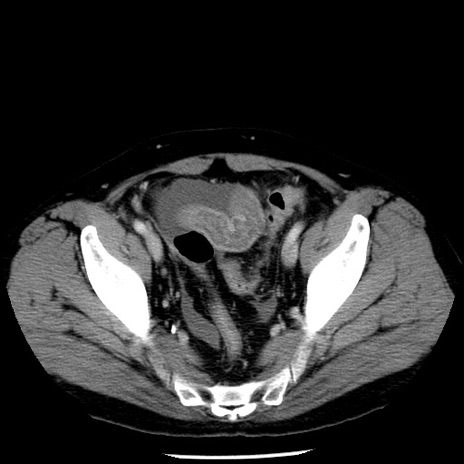

症例29(横断像)

【症例】40歳代男性

【現病歴】2日前から胃痛あり。徐々に周期的な激痛に変化した。本日になっても激痛があるため受診。

【身体所見】意識清明、BT 38-39℃台あり、腹部:膨満、やや硬、右下腹部に圧痛あり。

【データ】WBC 8500、CRP 23.26